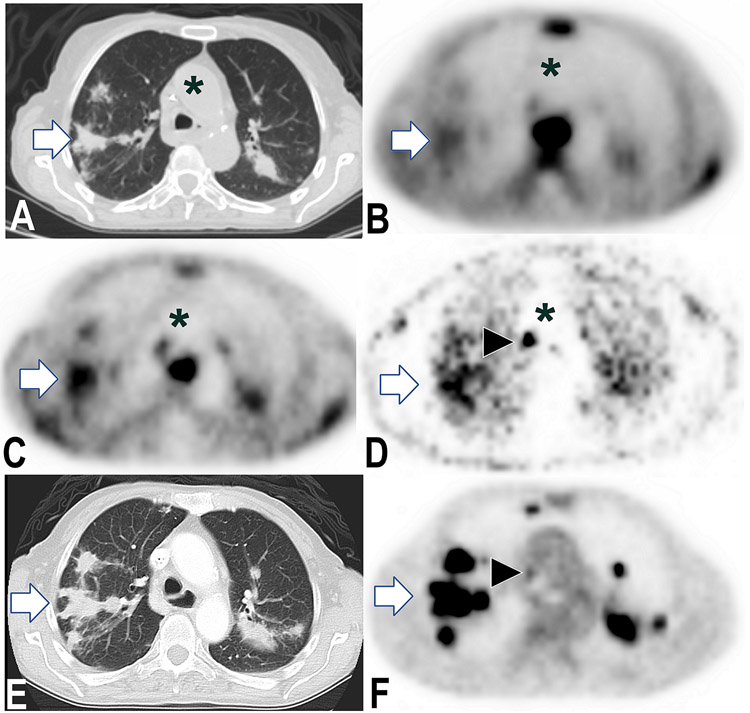

Figure 1.

Metastases demonstrate sustained PU-H71 retention one week post-injection. 76-year-old female with stage IV pancreatic cancer, on three-month chemotherapy vacation. PET and CT images show corresponding axial planes of chest. 124I-PU-H71 PET images obtained 3, 24, and 192 hours post-injection (B, C, and D, respectively) show rapid tracer clearance from blood (asterisk, aorta) with sustained PU-H71 retention by pulmonary metastases (e.g., right lung mass, arrow) and nodal metastases (e.g., arrowhead). Between 3 and 24 h (B and C), tumor:bloodpool SUV ratio value increased 371% (3 and 24 h ratios 4.2 and 19.8, respectively). Corresponding images from standard F-18 fluorodeoxyglucose (FDG) PET/CT images (E and F) obtained 2 days prior.

PET demonstrated the feasibility of tumor detection in humans by epichaperome-targeted imaging, visualizing tumor-selective PU-H71-targeting in vivo (Figs. 1-2, Supplementary Figs. 4-5). Our clinical PET data indicates the presence of tumor epichaperome formations in a variety of cancer types, as previously demonstrated preclinically (1). PU-H71-avid tumors were detected in 58% of patients (n=26, Table 1), significantly higher in PU-H71 concentration than non-avid tumors, in terms of SUV, tumor:bloodpool and tumor:muscle ratios at 24 hours (Supplementary Table 2). Evaluated tumors ranged in size from 0.8 to 4.5 cm (1.6 ± 0.5 cm average/SD). Contrary to rapid PU-H71 clearance from blood over a few hours, seen in all patients (as above), prolonged tracer retention in PU-H71-avid tumors was evident on PET imagery over a period of days (up to one week post-injection, Fig. 1). Across the patient population, rapid blood clearance yielded tumor:bloodpool ratios of radiotracer concentrations up to 14.4 at 4 hours (3.2± 3.0 average/SD) and up to 13.1 at 24 hours (3.9 ± 4.4 average/SD) post-injection (Figs. 1 and 2, Supplementary Fig. 2), consistent with specific PU-H71-binding to tumors, observed sustained for days beyond drug clearance from plasma.